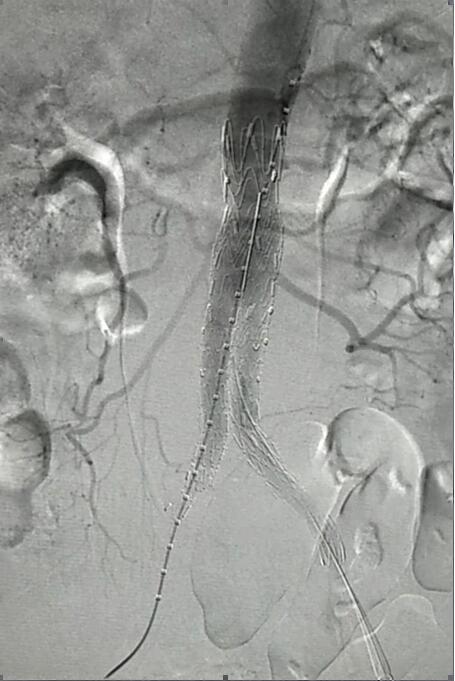

患者因腹部搏動(dòng)性腫塊行成已有4年,伴右下腹疼痛6小時(shí)入院,既往有高血壓病史,患者入院后血壓177/96mmHg,醫(yī)護(hù)人員隨即予以控制血壓、止痛處理,CTA檢查提示患者有腎下腹主動(dòng)脈瘤,合并心 、肝 、肺 、腎等重要臟器疾患,根據(jù) Laplace定律,動(dòng)脈瘤直徑越大壓力越大,老人動(dòng)脈脆弱,動(dòng)脈瘤隨時(shí)有破裂的可能性,其危險(xiǎn)性大。血管介入科排除各種困難,在麻醉科協(xié)作下行腹主動(dòng)脈瘤覆膜支架隔絕術(shù)(“褲衩”支架植入),手術(shù)持續(xù)了1個(gè)半小時(shí),患者術(shù)后安返病房,麻醉醒后露出了微笑,向醫(yī)務(wù)人員伸出大拇指。

血管介入科行腹主動(dòng)脈瘤覆膜支架隔絕術(shù)(“褲衩”支架植入)。圖2